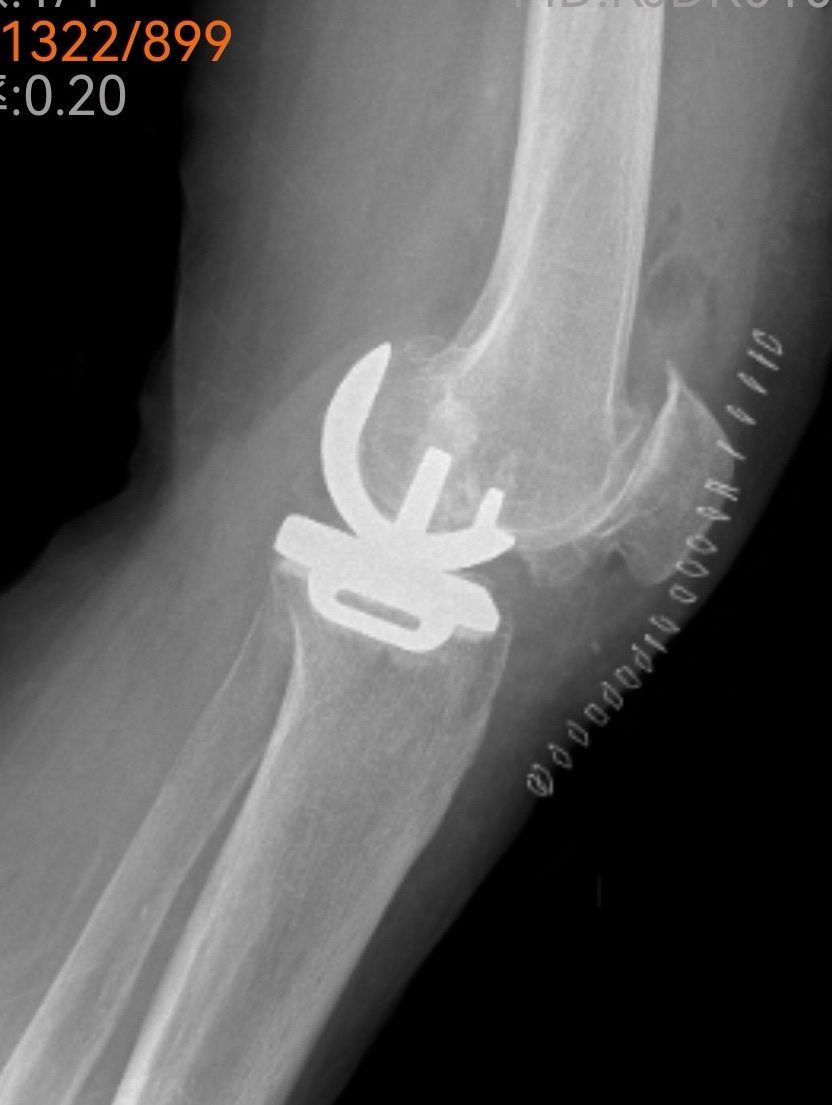

傳統(tǒng)的全膝關(guān)節(jié)置換固然能解決問題,但創(chuàng)傷較大、恢復(fù)期長(zhǎng)。經(jīng)過團(tuán)隊(duì)綜合評(píng)估,魏海清主任提出了一個(gè)更精細(xì)的方案:“我們建議行左膝關(guān)節(jié)單髁置換術(shù)。這就像牙齒壞了,我們不必把所有牙齒都換掉,而是只替換損壞的部分。這種手術(shù)只替換磨損的軟骨和部分骨質(zhì),能最大限度保留健康組織?!彼贸鱿リP(guān)節(jié)模型,耐心地向一家人解釋手術(shù)原理:“您看,膝關(guān)節(jié)分為內(nèi)側(cè)、外側(cè)和髕股三個(gè)部分。您的磨損主要集中在內(nèi)側(cè),所以我們只需置換這一部分。”這種個(gè)體化、精準(zhǔn)化的治療理念,讓原本忐忑的一家人逐漸安心。

微創(chuàng)手術(shù),一小時(shí)改寫生活

手術(shù)室里,骨科、麻醉科、手術(shù)室團(tuán)隊(duì)配合默契。微創(chuàng)切口僅有傳統(tǒng)手術(shù)的一半大小,精細(xì)的操作在關(guān)節(jié)鏡輔助下進(jìn)行。沒有大刀闊斧的創(chuàng)傷,只有精準(zhǔn)細(xì)致的重建。一小時(shí)后,手術(shù)順利結(jié)束,出血量?jī)H約100毫升。“這么快?”等候在外的兒子們幾乎不敢相信。魏海清主任走出手術(shù)室,微笑點(diǎn)頭:“很順利,單髁置換本來就是微創(chuàng)手術(shù),對(duì)患者損傷小?!?/p>

出院前,李阿姨特意換上了從家鄉(xiāng)帶來的紅色外套,與醫(yī)療團(tuán)隊(duì)合影留念。鏡頭前,她的笑容燦爛而真實(shí)。魏海清主任看著這位千里求醫(yī)的患者,心中感慨:“上了年紀(jì)的人最怕關(guān)節(jié)問題導(dǎo)致無法活動(dòng)。長(zhǎng)期臥床會(huì)引起一系列并發(fā)癥,嚴(yán)重影響生活質(zhì)量。我們采用的改良微創(chuàng)手術(shù),出血少、損傷小、恢復(fù)快,符合快速康復(fù)理念?!彼D了頓,繼續(xù)說道:“患者跨越兩千多公里選擇我們,這份信任沉甸甸的。作為醫(yī)生,我們唯有以精湛技術(shù)和全心關(guān)懷相回報(bào),才不負(fù)這份生命的托付。”